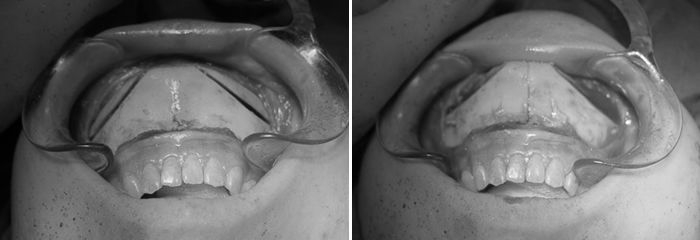

手術中の写真